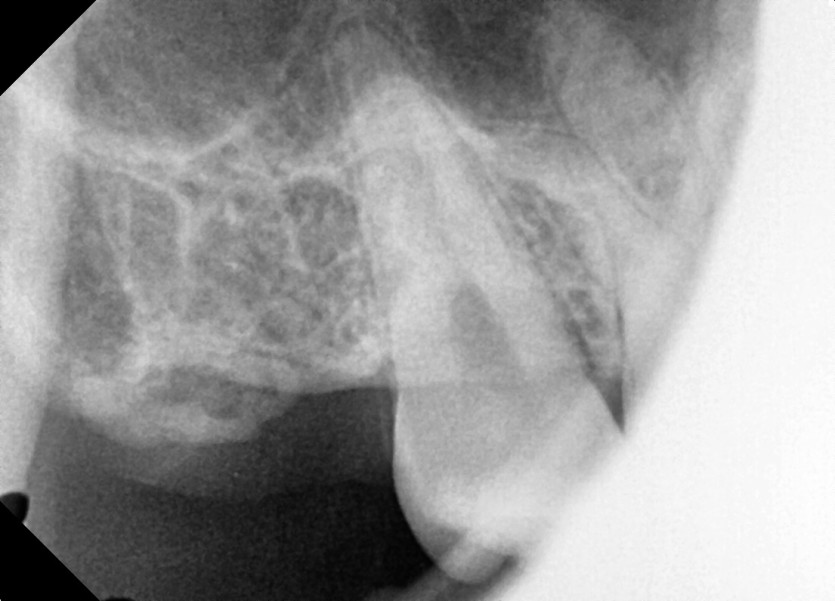

#18,48 사랑니 발치

구강 외과 전문의가 당일 발치했습니다.